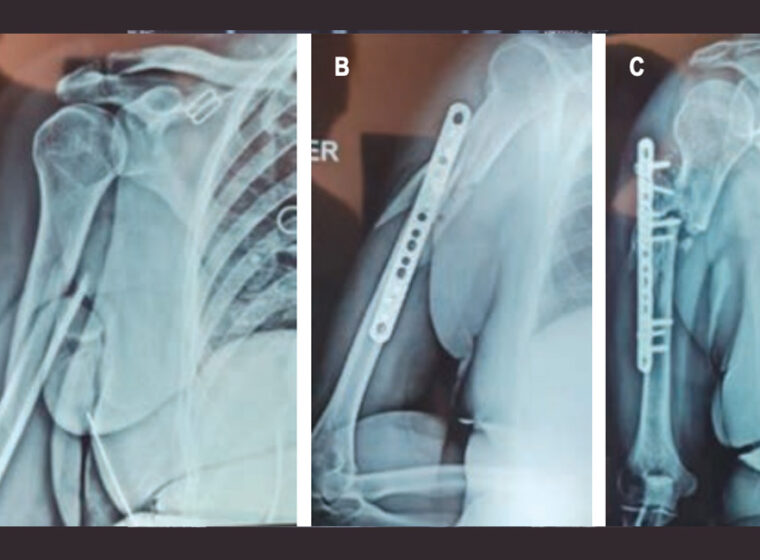

Protocolos efectivos para pseudoartrosis refractaria de húmero mediante injerto tricortical e instrumentalación especializada